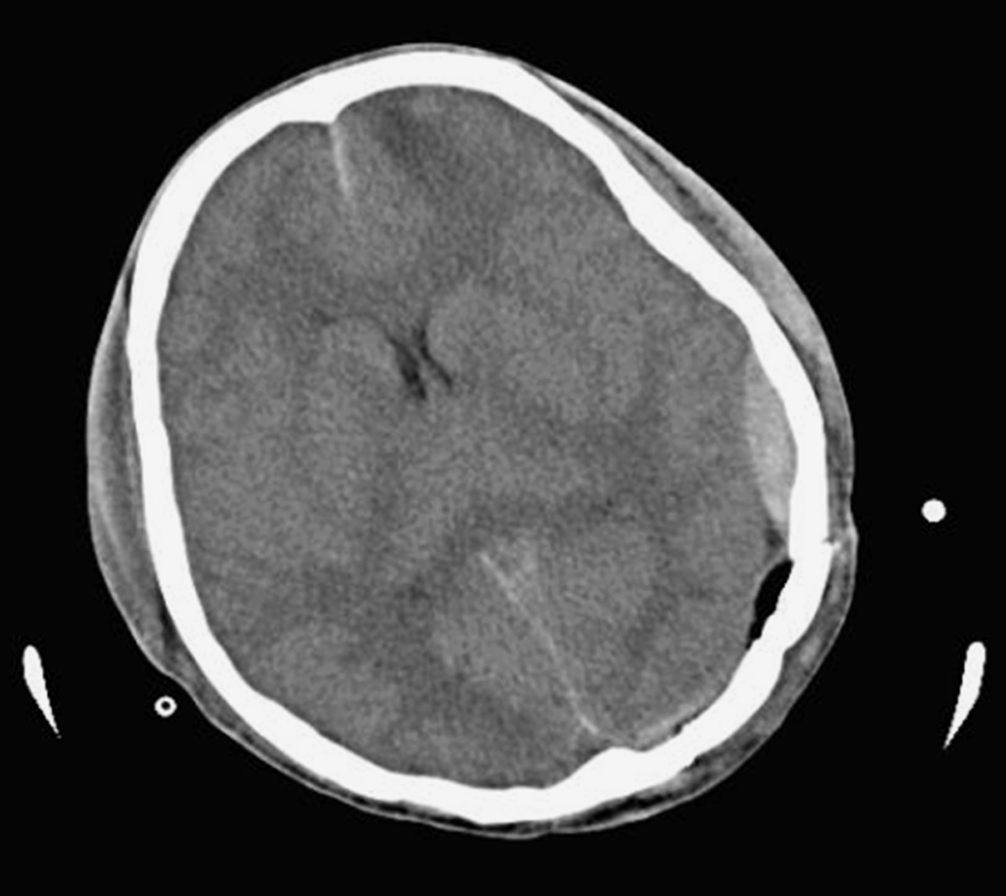

CT表现:损伤区局部呈低密度改变,其大小可从几厘米至全脑,形态不一,边缘模糊,白质区明显,约有1/3为多发病灶。低密度区数天至数周后,有些可以恢复至正常脑组织密度,有些进一步发展为更低密度区,提示脑组织软化(图2-4-5)。

图2-4-5 脑挫裂伤CT影像表现

CT和MR检查:均在损伤2h后可见点状或斑片状高密度出血灶,挫裂伤范围越大,占位效应和脑水肿越明显,表现为同侧脑室受压,中线结构移位,重者出现脑疝征象。水肿高峰期过后,占位征象逐渐减轻,后期出现脑萎缩征象。低密度区数天至数周后,有些可以恢复至正常脑组织密度,有些进一步发展为更低密度区,提示脑组织软化。挫裂伤重而且范围大,后期可出现脑内囊性病灶。